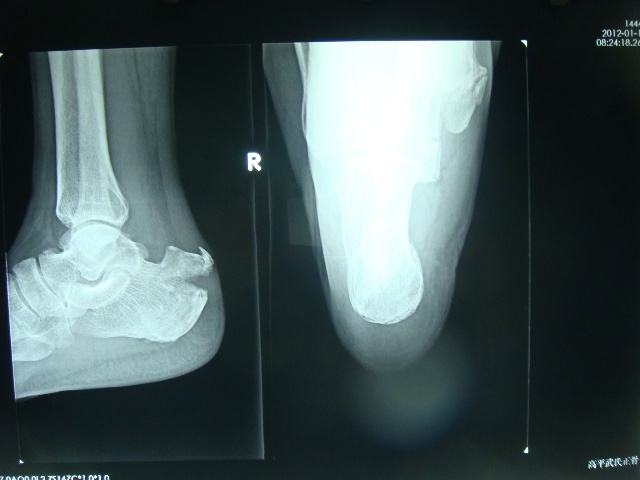

第二种情况,跟骨高度,宽度,关节面不正常,或者骨折片移位太明显,那么需要手术,手术后的的除了伤口需要换药,不用打石膏,可以马上进行锻炼,同时定时冰敷,可以防止减轻疼痛,防止僵硬,促进消肿,其他类似!抬高患肢和活动足趾,然后逐渐活动膝关节,然后活动踝关节,我认为是最重要的!也可以应用一些消肿的药物,快速消肿极为重要!

无论哪种方式,要下地活动都需要拍片复查确认骨折已经愈合才可以,跟骨负担全身重量,如果不牢固,走路很容易出现再次骨折!所以一定要谨慎。顺便说一句,吃药对于骨折的愈合有没有提前的作用呢?我个人认为是没有的,我还没有发现任何证据证明任何药物可以让骨折提前愈合,骨折愈合时间主要取决于正确的锻炼,良好的康复,身体素质,没有并发症。但药物是不是一点作用都没我呢?不是,可以预防延迟愈合或者不愈合!当然不是一定的!因为也没证据!